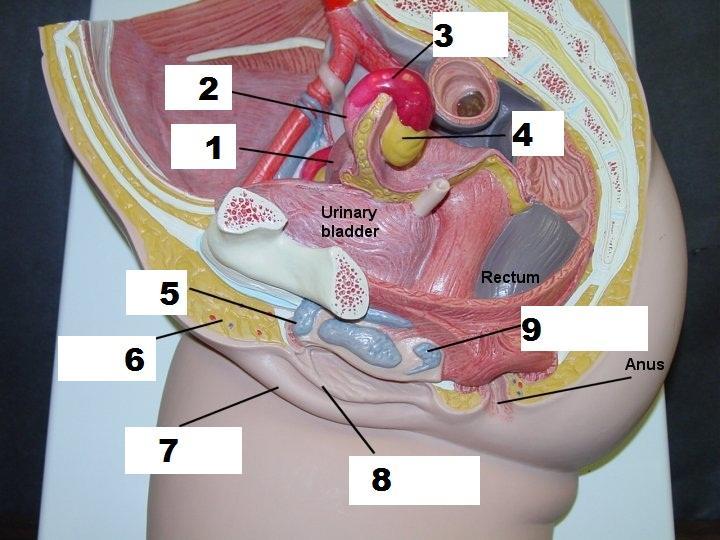

Anal Canal

Anus

Cervix

Clitoris

Common iliac artery/vein

External urethral orifice (female)

Internal/external iliac artery/vein

Labia majora/minora

Rectum

Ureter

Urethra

Urinary Bladder (female)

Uterine (=fallopian) tube

Uterus

Vagina

Vaginal orifice

Vestibule (of vulva)